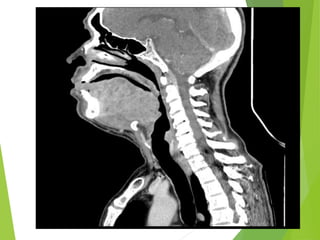

Estudios de imagen

20 de Marzo 2013

Estudios de Imagen:

-TAC de cuello simple y contrastado

20 de Marzo2013 Estudios de Imagen: -TAC de cuello simple y contrastado